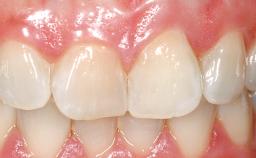

A 30-year-old female patient was referred to the office for the treatment of tooth 11. Her chief concern at the initial visit was to inquire, “Why is my tooth pink?” Upon clinical examination, it was determined that tooth 11 had a previous history of trauma and that the clinical crown had become noticeably pink in color as a result of internal resorption. This diagnosis was confirmed radiographically, indicating a large radiolucency involving the central and distal portions of the clinical crown. It was determined that restoration of this tooth was not possible, and that extraction was indicated. The presence of a mid-line diastema, which the patient wanted to reproduce, directed the treatment plan for tooth replacement utilizing a dental implant.

Mesio-Distal Space Asymmetry greater than 1 mm

Esthetic Risk High